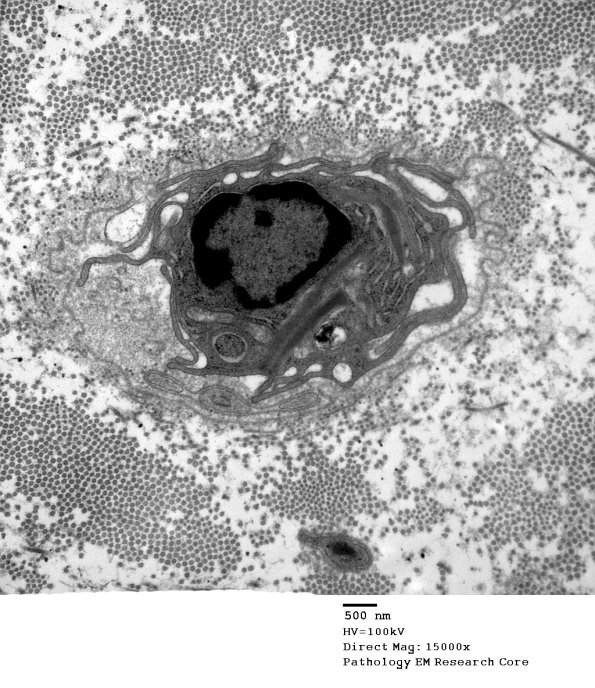

A macrophage is alone within the original basement membrane of the degraded Schwann cell.